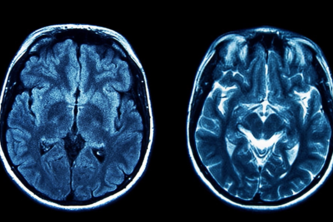

MRI Smart Scan uses AI to quickly analyze MRI images, detecting Alzheimer's and brain tumors early, providing healthcare professionals with fast, reliable diagnostic insights for better patient care.